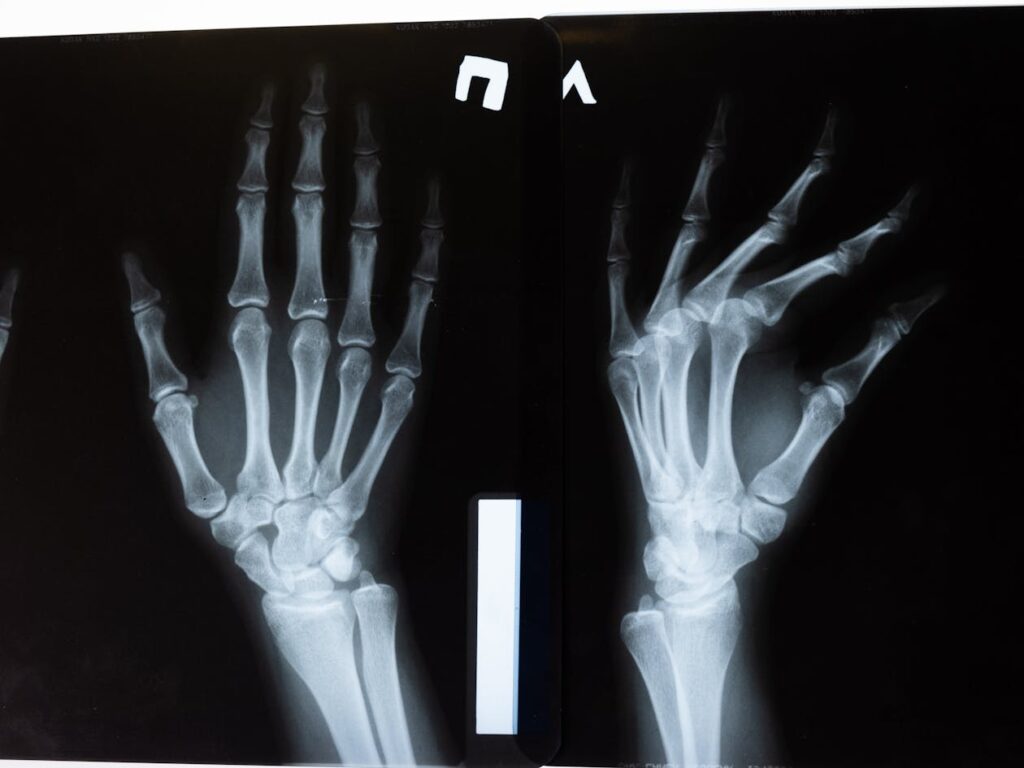

Young animals developed osteoporosis-like symptoms rapidly despite normal diet and activity levels. Bone density measurements revealed significantly reduced cortical thickness and trabecular number compared to normal mice. Microscopic analysis showed fewer osteoblasts present and reduced bone formation rates.

Three-point bending tests confirmed functional consequences. Bones from knockout animals broke more easily under mechanical stress despite seemingly modest density reductions. Even heterozygous mice carrying one functional and one non-functional gene copy showed intermediate phenotypes with measurable bone weakness.

Trabecular bone parameters improved across multiple measurements. Number of trabecular struts increased. Individual trabeculae grew thicker. Spacing between struts decreased as bone filled previously empty regions. Cortical bone showed increased thickness and density.

Biomechanical testing validated functional improvements. Femurs from treated mice tolerated higher loads before fracturing. Elastic modulus measurements indicated stiffer, more resistant bone tissue capable of better withstanding daily mechanical stresses.